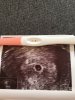

Ale wizyta się odbyła. Na usg widoczny pęcherzyk. Jak to doktor powiedział „prawidłowa wczesna ciąża wewnątrzmaciczną” [emoji7][emoji7][emoji7][emoji7]

I to były wspaniałe wieści [emoji3590]

Warto było jechać dla tego widoku [emoji3590][emoji3590] Jak mąż wróci to wrzuce fotkę.

Za dwa tygodnie będziemy sprawdzać czy w tym pęcherzyku jest zarodek z serduszkiem [emoji3590]